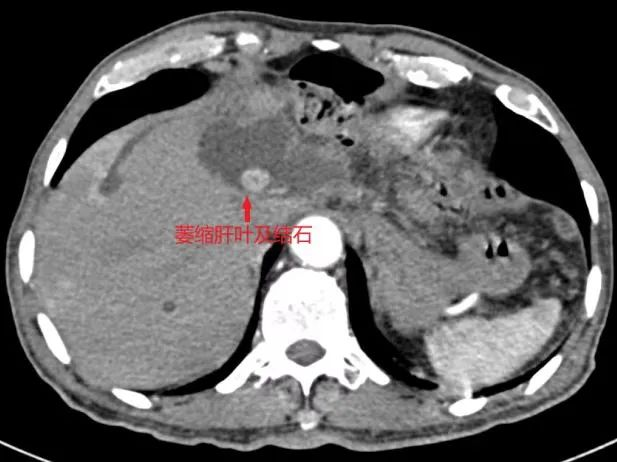

患者入院后,肝胆胰脾外科团队为患者完善了CT、MRCP等检查,发现患者并不是简单的胆囊结石,而是复杂的肝左叶胆管结石伴左肝叶及左尾状叶萎缩。临床上肝内胆管结石反复并发感染,可引起局部肝脏的萎缩、纤维化和功能丧失,甚至癌变。切除病变部分的肝脏,是根治肝内胆管结石的**方法。而肝切除术是非常具有挑战力的手术,手术区域解剖变异多、术中出血不易控制、还有气体栓塞等风险。

针对这例复杂的肝内胆管结石,尤其是作为“肝脏手术禁区”的尾状叶切除术,肝胆胰脾外科主任袁建毛组织科室医护人员经过详细的术前讨论,制定了完善的手术方案。在麻醉科曹晖副主任医师的全程精心护航下,经过三个多小时的手术,成功实施了左半肝切除术+左尾状叶切除术+胆囊切除术+经左肝管胆道胆管探查术。术后病理提示:肝脏导管内乳头状肿瘤伴低级别上皮内肿瘤,局部腺体中度异型增生,慢性胆囊炎。在23病区全体医护人员的精心治疗和护理下,患者顺利康复出院。